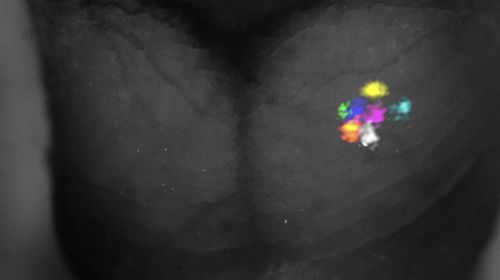

Investigadores del CBM y el ISCIII revelan la especialización de las isoformas de Ras en la función neuronal

Un equipo de investigadores del Centro de Biología Molecular Severo Ochoa (CBM-CSIC-UAM) y del Instituto de Salud Carlos III (ISCIII)...

El cerebro en desarrollo puede reorganizar sus mapas sensoriales tras una pérdida temprana del tacto

Un estudio del Instituto de Neurociencias (CSIC-UMH), publicado en Nature Communications, demuestra que el cerebro en desarrollo reorganiza...